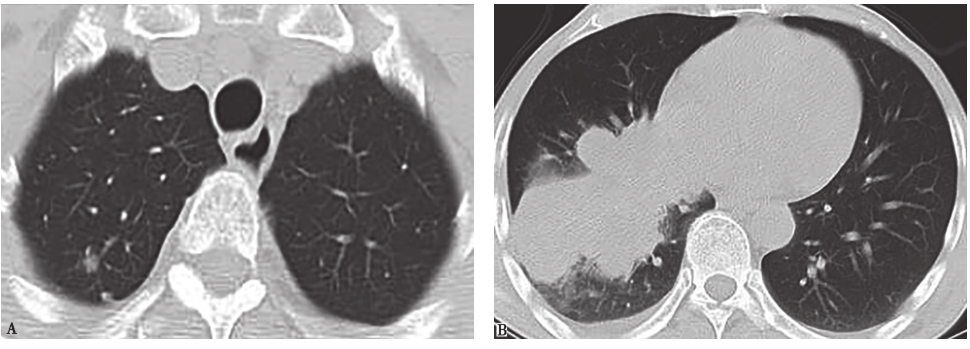

胸部CT:右肺下叶病变伴远端肺阻塞性改变,右肺门及纵隔淋巴结肿大,右肺上叶结节,右侧胸腔积液(图1)。

图1 入院前2天胸部CT表现

胸部CT可见右肺上叶结节,右下肺实变伴胸腔积液